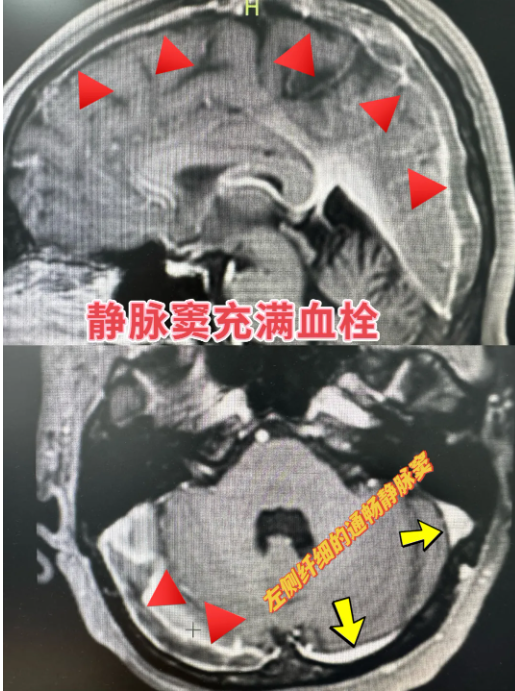

腦中風(fēng),讓人聞“風(fēng)”色變,我們熟知的“腦梗死”通常指腦動(dòng)脈系統(tǒng)發(fā)生“交通堵塞”,出現(xiàn)意識(shí)障礙、偏癱、語(yǔ)言功能障礙等癥狀,以老年患者居多,而主攻年輕群體的靜脈系統(tǒng)血栓卻鮮為人知。顱內(nèi)靜脈竇血栓形成(Cerebral venous thrombosis, CVT)是一種少見(jiàn)且兇險(xiǎn)的腦血管病,約占腦血管病的0.5%-1%,臨床表現(xiàn)復(fù)雜多樣,主要為顱高壓,甚至腦梗死或者腦出血,常見(jiàn)癥狀有頭痛、視物模糊、癲癇和局灶性神經(jīng)功能障礙等,早期診斷困難,且有非常高的致殘率和致死率。

因?yàn)槟X靜脈竇變異多,且腔道內(nèi)分隔多,靜脈竇疾病介入治療是神經(jīng)科介入手術(shù)中難度系數(shù)較高、操作較為復(fù)雜的手術(shù)之一,它要求手術(shù)醫(yī)生具備精湛的專(zhuān)業(yè)技術(shù)、豐富的臨床經(jīng)驗(yàn)以及較強(qiáng)的應(yīng)變能力,嵊州市人民醫(yī)院(浙大一院嵊州分院)神經(jīng)內(nèi)科開(kāi)展腦血管介入診療正好10年,為此手術(shù)的順利開(kāi)展積累了足夠的經(jīng)驗(yàn)和堅(jiān)實(shí)的技術(shù)基礎(chǔ)。同時(shí),此類(lèi)高難度手術(shù)的成功開(kāi)展,標(biāo)志著嵊州市人民醫(yī)院(浙大一院嵊州分院)卒中中心腦卒中救治能力上了一個(gè)臺(tái)階,能更好地為區(qū)域內(nèi)腦卒中患者保駕護(hù)航。